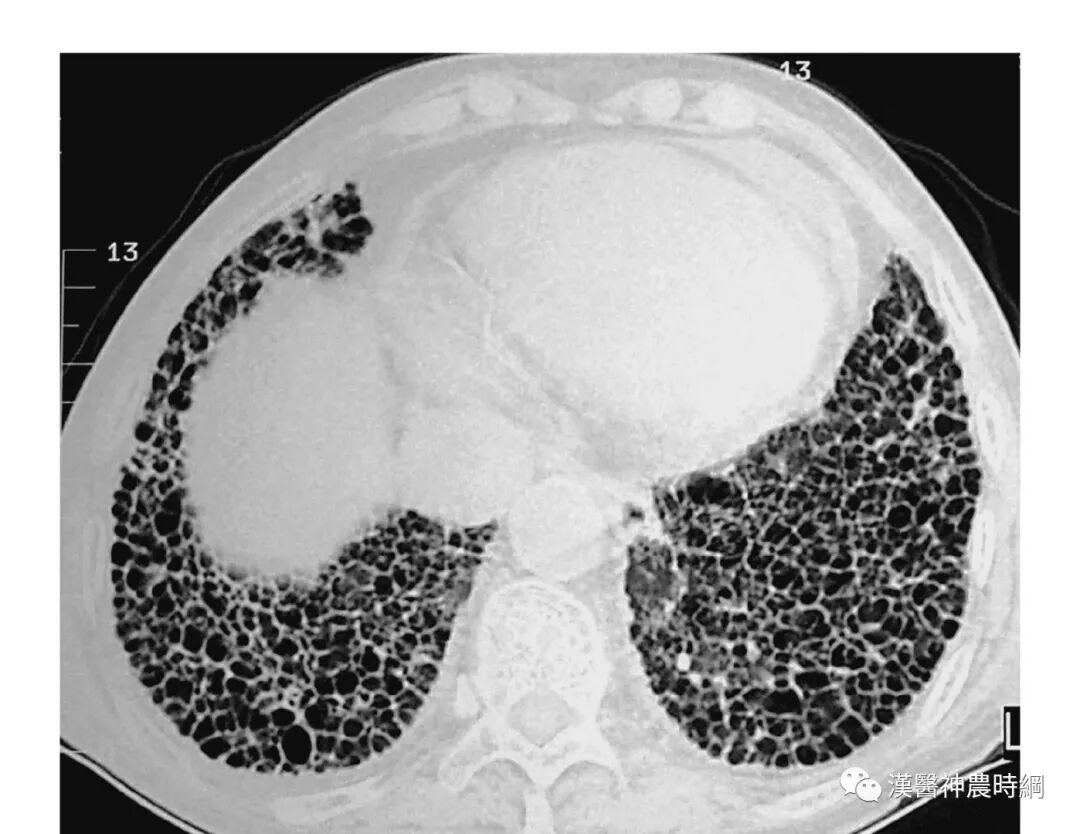

大多数间质性肺疾病都有共同的病理基础过程。初期损伤之后有肺泡炎,随着炎性-免疫反应的进展,肺纤维化泡壁、气道和血管最终都会发生不可逆的肺部瘢痕(纤维化)。炎症和异常修复导致肺间质细胞增殖,产生大量的胶原和细胞外基质。肺组织的正常结构为囊性空腔所替代,这些囊性空腔有增厚的纤维组织所包绕,此为晚期的“蜂窝肺”。肺间质纤维化和“蜂窝肺”的形成,导致肺泡气体-交换单元持久性的丧失。

一般情况下,肺纤维化早期出现肺泡炎,肺泡内有浆液和细胞成分,肺间质内有大量单核细胞,部分淋巴细胞,浆细胞,肺泡巨噬细胞等炎性细胞浸润,肺泡结构完整。进入晚期,慢性炎症已减轻,肺泡结构为坚实的胶原代替,肺泡壁被破坏,形成扩张的蜂窝肺。胶原、细胞外基质、成纤维细胞分布在间质中,肺泡上皮化生为鳞状上皮。

早期虽有呼吸困难,但X线胸片可能基本正常;中后期出现两肺中下野弥散性网状或结节状阴影,偶见胸膜腔积液,增厚或钙化。肺组织纤维化的严重后果,导致正常肺组织结构改变,功能丧失。就是大量没有气体交换功能的纤维化组织代替肺泡,导致氧不能进入血液。患者呼吸不畅,缺氧、酸中毒、丧失劳动力、靠呼吸机生存,最后衰竭、死亡。

(3)从临床特点而言,肺间质纤维化病程日久,迁延不愈,“初病气结在经,久则血伤入络”,晚期呈蜂窝肺(网格状改变),甚至毁损肺,肺功能丧失殆尽。此恰似肺痿沉疴之肺叶萎弱不用,迁延反复,久治不愈之特点。